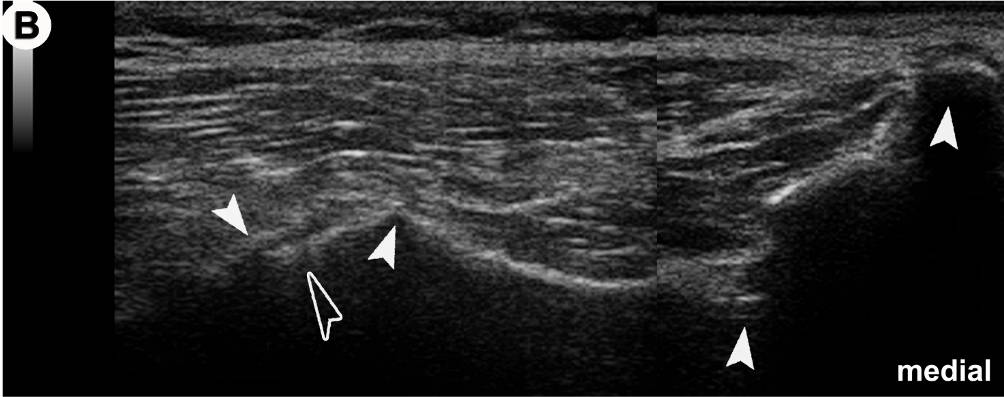

Anatomischer Transversalschnitt (A) und korrespondierendes US-Bild (B) auf Ebene des Foramen sacrale posterius secundum (II): Grundlage für die US-gezielte Injektion des Iliosakralgelenkes (ISG).

In der US-Darstellung ist der dorsalste Anteil des ISG einsehbar (offener Pfeilkopf). Der Spalt entspricht dem radiologischen Gelenkspalt! Die knöchernen Landmarken (gefüllte Pfeilköpfe) sind aber in allen Details deutlich zu erkennen (von medial nach lateral): Crista sacralis mediana, II, Crista sacralis lateralis, Facies glutea ossis ilii.